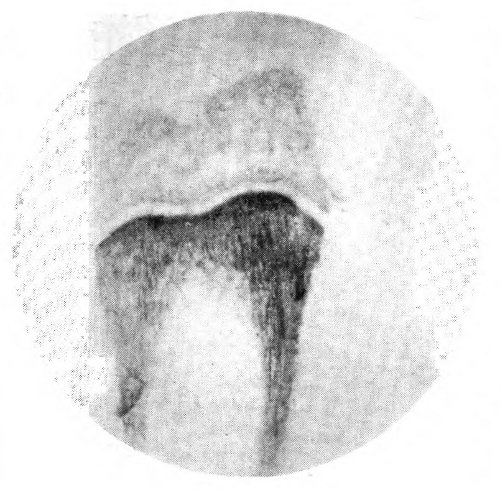

5. Leg bone of a rabbit after injection of Sr⁸⁹.

6. Leg bone of a woman dead of radium poisoning.